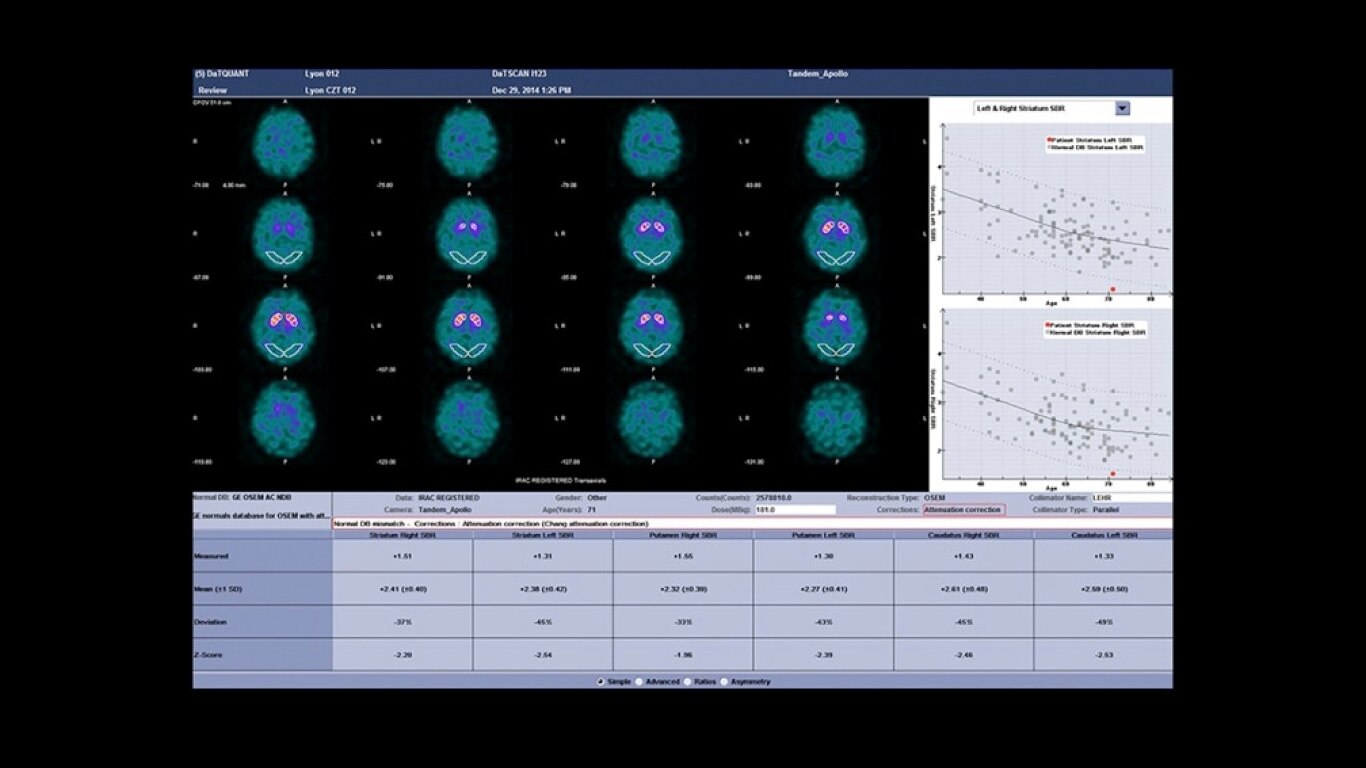

Experience a new productivity hub for hybrid imaging. By automating SPECT/CT reconstruction, SmartConsole simplifies the workflow for complex hybrid and quantitative protocols and allows technologists to review results directly at the scanner console. It also allows physicians to review scans remotely from mobile devices. They can modify processing settings and initiate study processing anytime, anywhere across a LAN or a WAN*.

SmartConsole enables a noticeable improvement in productivity. Now, a physician can provide their input remotely and digitally. For example, physicians can review a whole-body bone scan directly on their tablet or other mobile device and define the scan range limits they need from wherever they are. The time saved with this switch to a digital workflow helps make it possible to complete exams in predictable time slots.